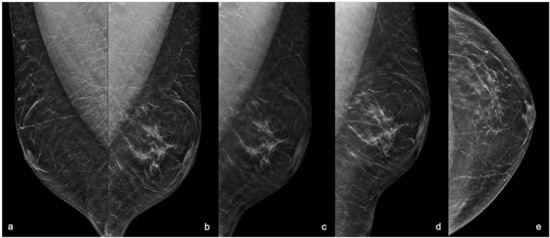

2. Case Report